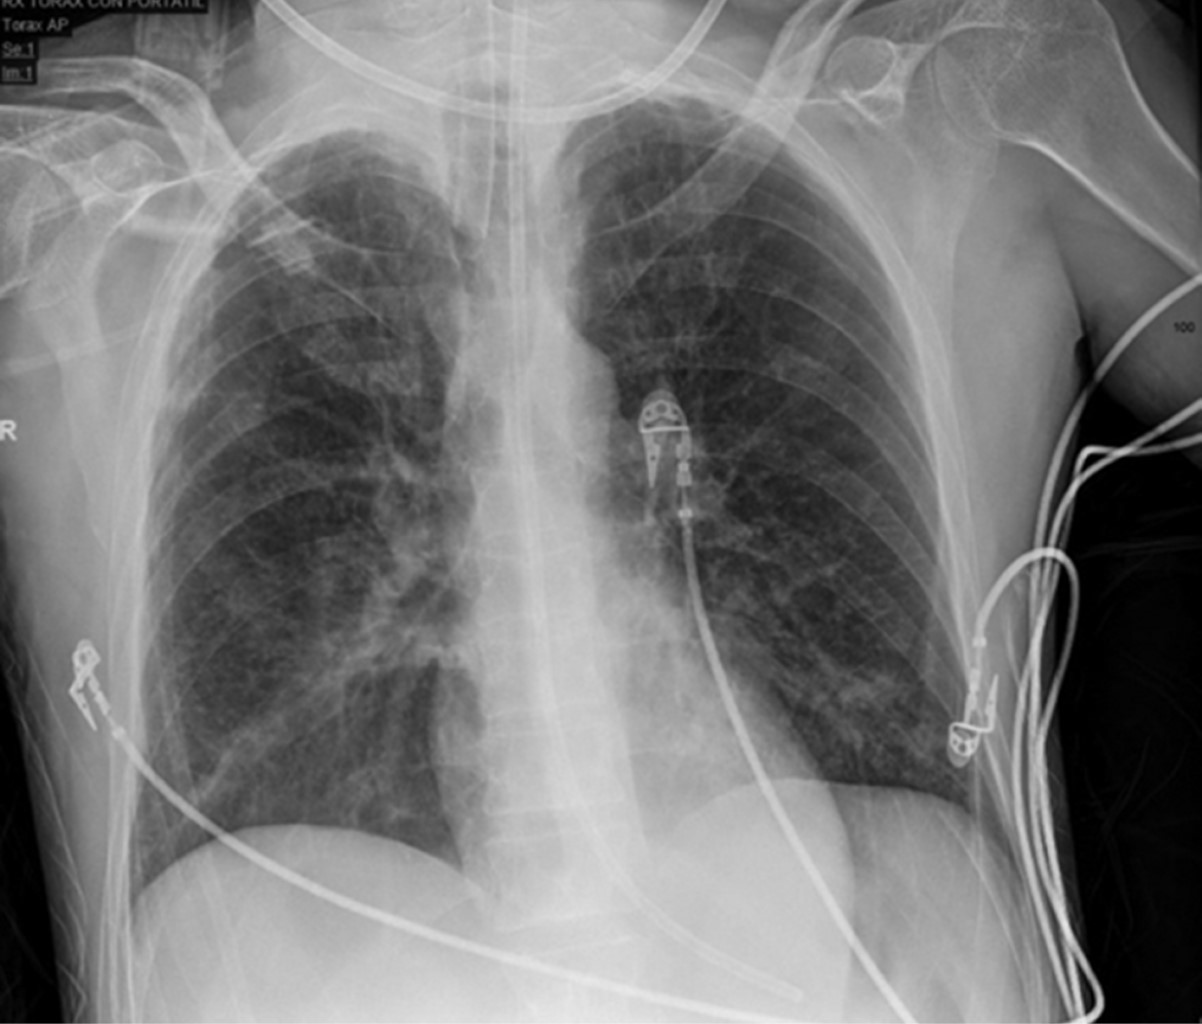

Figura 1